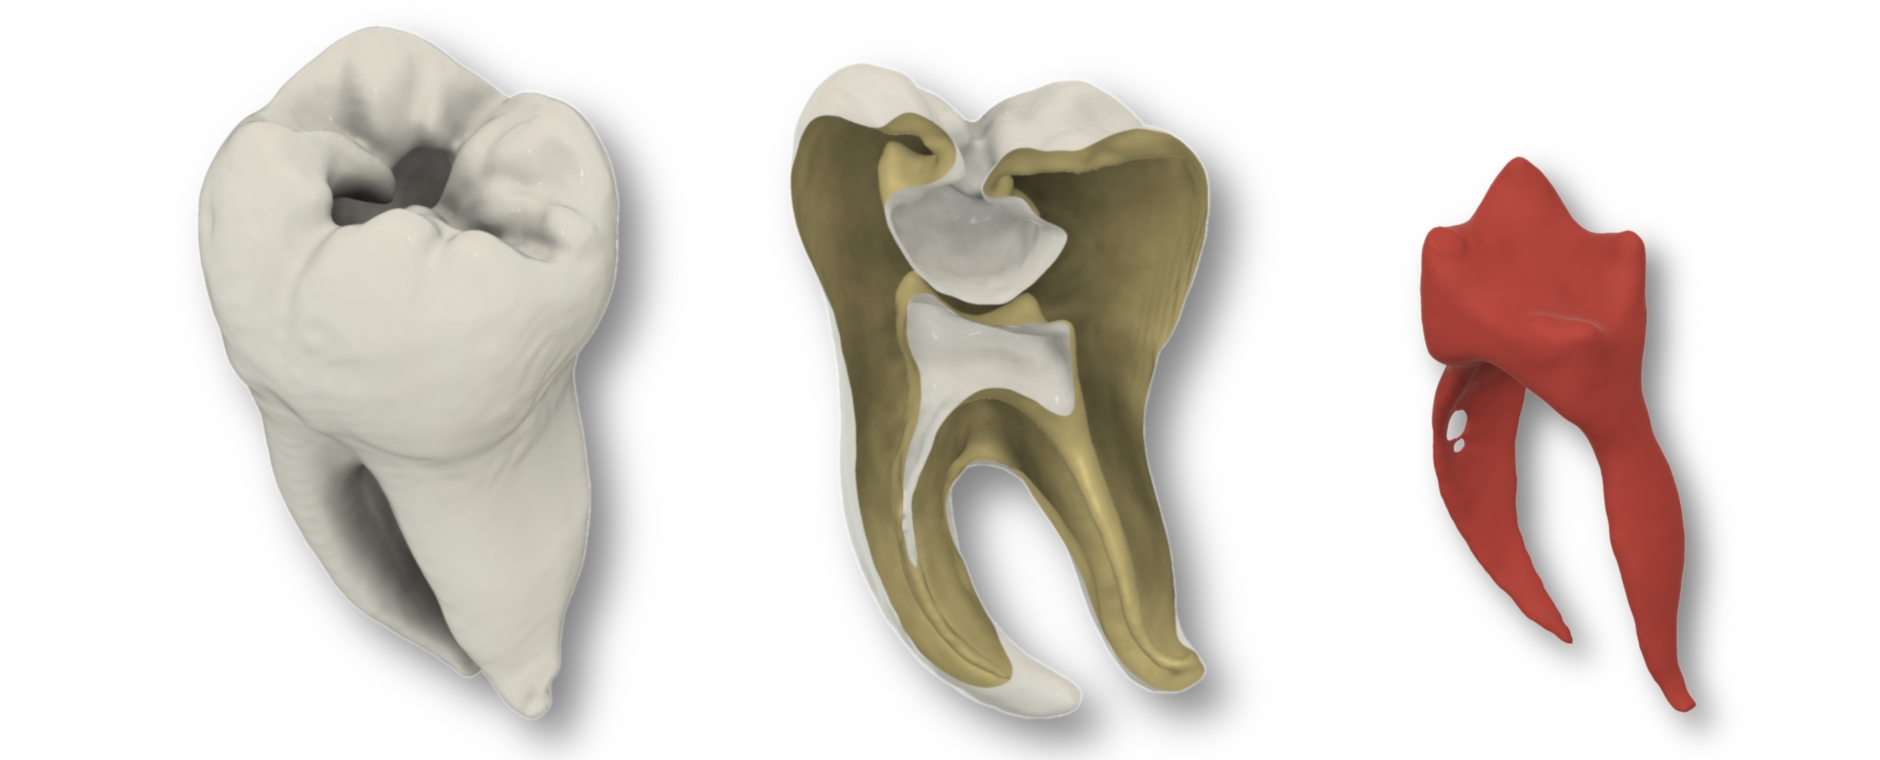

Studien belegen den hohen Lerneffekt, die Akzeptanz bei Studierenden und den didaktischen Nutzen des universellen Übungszahns bei einer Kariesexkavation und beim Präparieren von Klebebrücken belegten bereits Studien im Journal BMC Medical Education und in Scientific Reports. Jetzt wurde die Erprobung des 3D-gedruckten Zahns bei der Wurzelkanalbehandlung veröffentlicht.

38 Zahnmedizinstudierende bewerteten den 3D-gedruckten Zahn als eine signifikant bessere Übungsmöglichkeit als die üblichen transparenten Acrylblöcke, die oft zum Üben für Wurzelkanalbehandlungen zum Einsatz kommen, und fast ebenbürtig zu natürlichen Zähnen, insbesondere hinsichtlich Realismus, Handhabung und Lernwert. „Der gedruckte Zahn ist nicht nur realistisch und kosteneffizient, sondern auch fair. Mit dem neuen Übungszahn haben wir für alle Studierenden identische Prüfungs- und Lernbedingungen geschaffen“, resümiert Erstautorin Isabella Di Lorenzo.

Auch Oberarzt Dr. Michael del Hougne M.Sc., Kursleiter im Bereich der klinischen Lehre, ist vom neuen Übungszahn begeistert. „Unsere Studierenden können an dem Modell sogar die elektrische Längenmessung des Wurzelkanals sehr realistisch üben. Dafür mussten wir jedoch etwas tricksen, um die benötigte Leitfähigkeit herzustellen, denn der Zahn ist aus Harz, das den Strom nicht leitet.“ Im nächsten Schritt sollen 3D-Zähne mit unterschiedlichen Wurzelkanalformen entwickelt werden, um die klinischen Herausforderungen, die sich aus der anatomischen Vielfalt ergeben, zu simulieren.